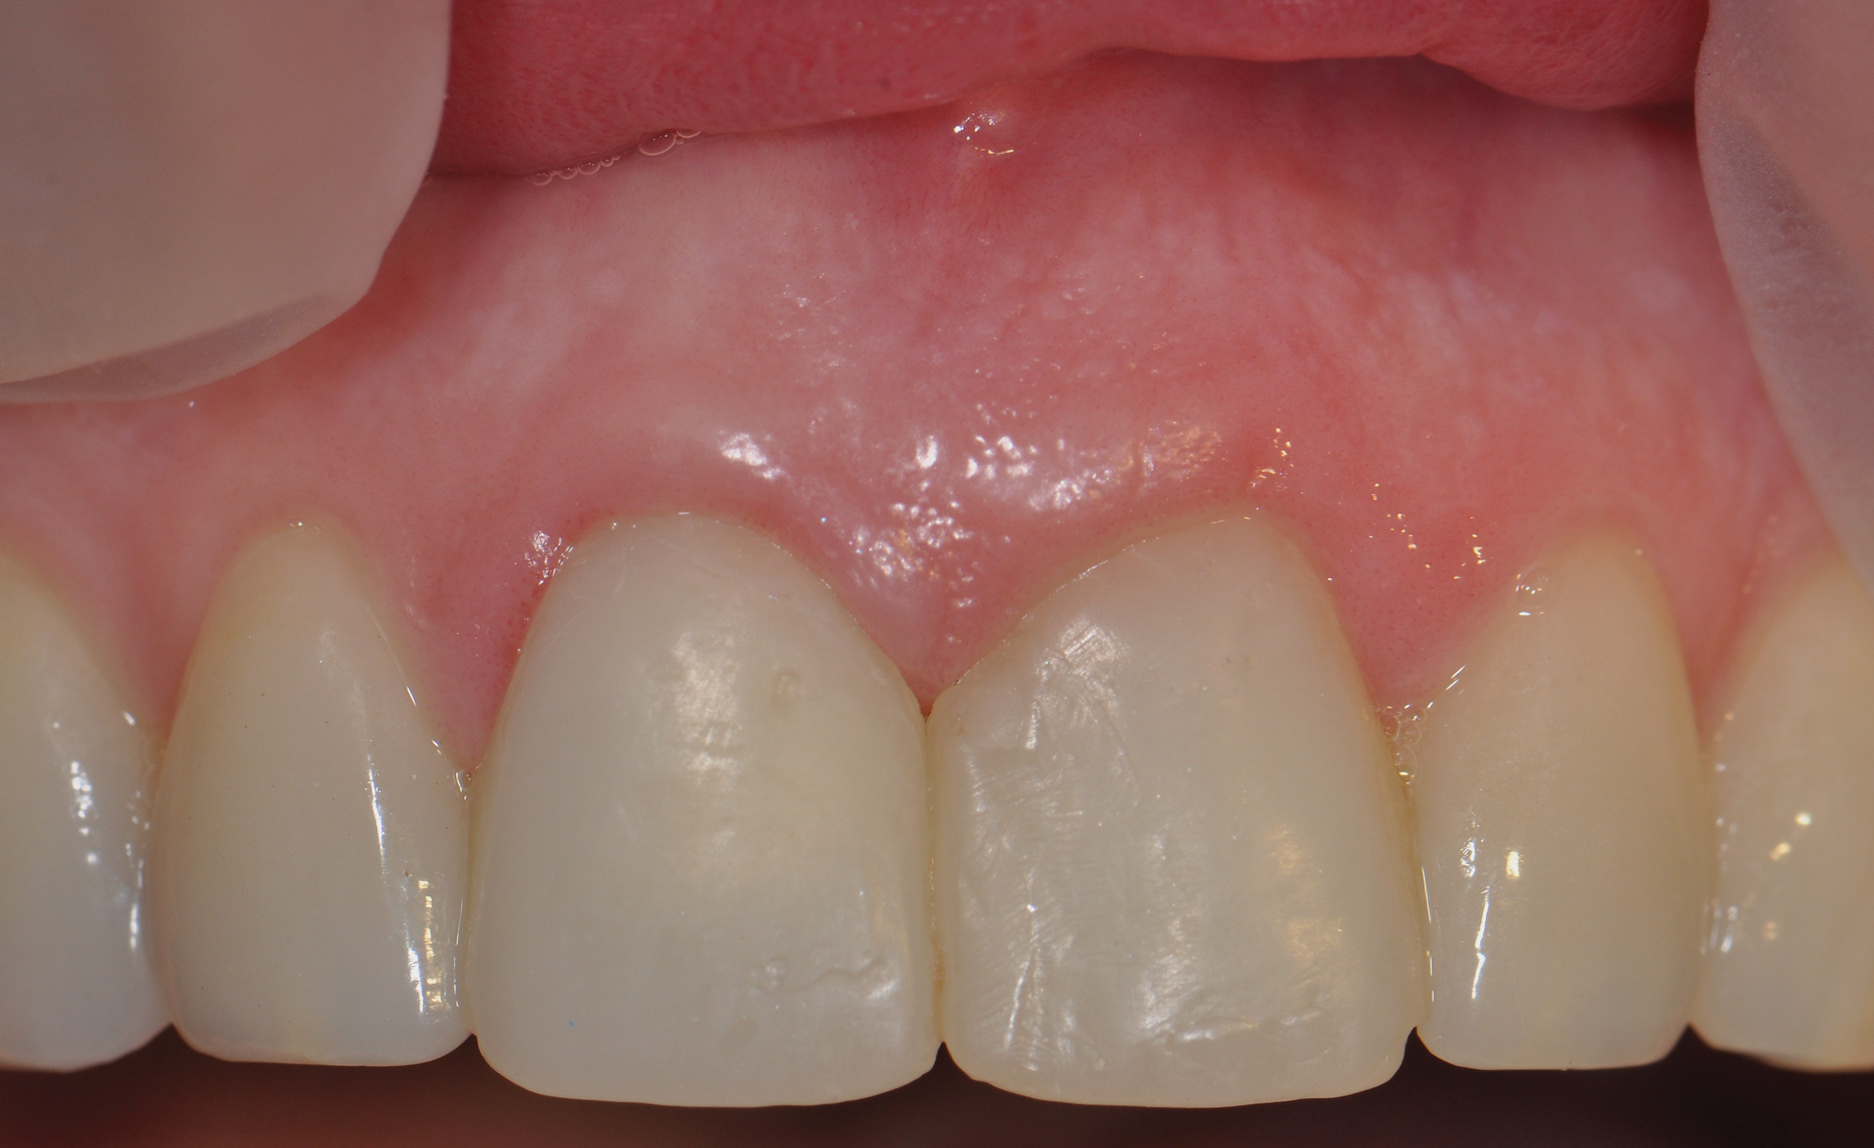

Figure 8 shows the provisionalization of No. 8 at 6 weeks postoperatively and a screw-retained provisional restoration on No. 9 to develop the subgingival transitional zone (key Nos. 8 through 10). The transitional zone will be duplicated using the custom impression coping technique. Figure 9 and Figure 10 depict the completed crowns at 5 years; implant No. 9 was screw-retained (key No. 10). In Figure 10 note the convex contours facial to implant No. 9 that are attributed to the connective tissue grafting as part of the surgical protocol creating biotype conversion from a thick to a thicker biotype. Figure 11 through Figure 13 show 5-year postoperative patient smile, periapical x-ray, and CBCT, respectively.

Fig 9. Completed crowns at 5 years, front view. Implant No. 9 was screw-retained (periodontist: Robert A. Levine, DDS; restorative dentist: Zola Makrauer, DMD).

Figure 9

Fig 10. Completed crowns at 5 years, angled view. Note the convex contours facial to implant No. 9 attributed to the connective tissue grafting.

Figure 10